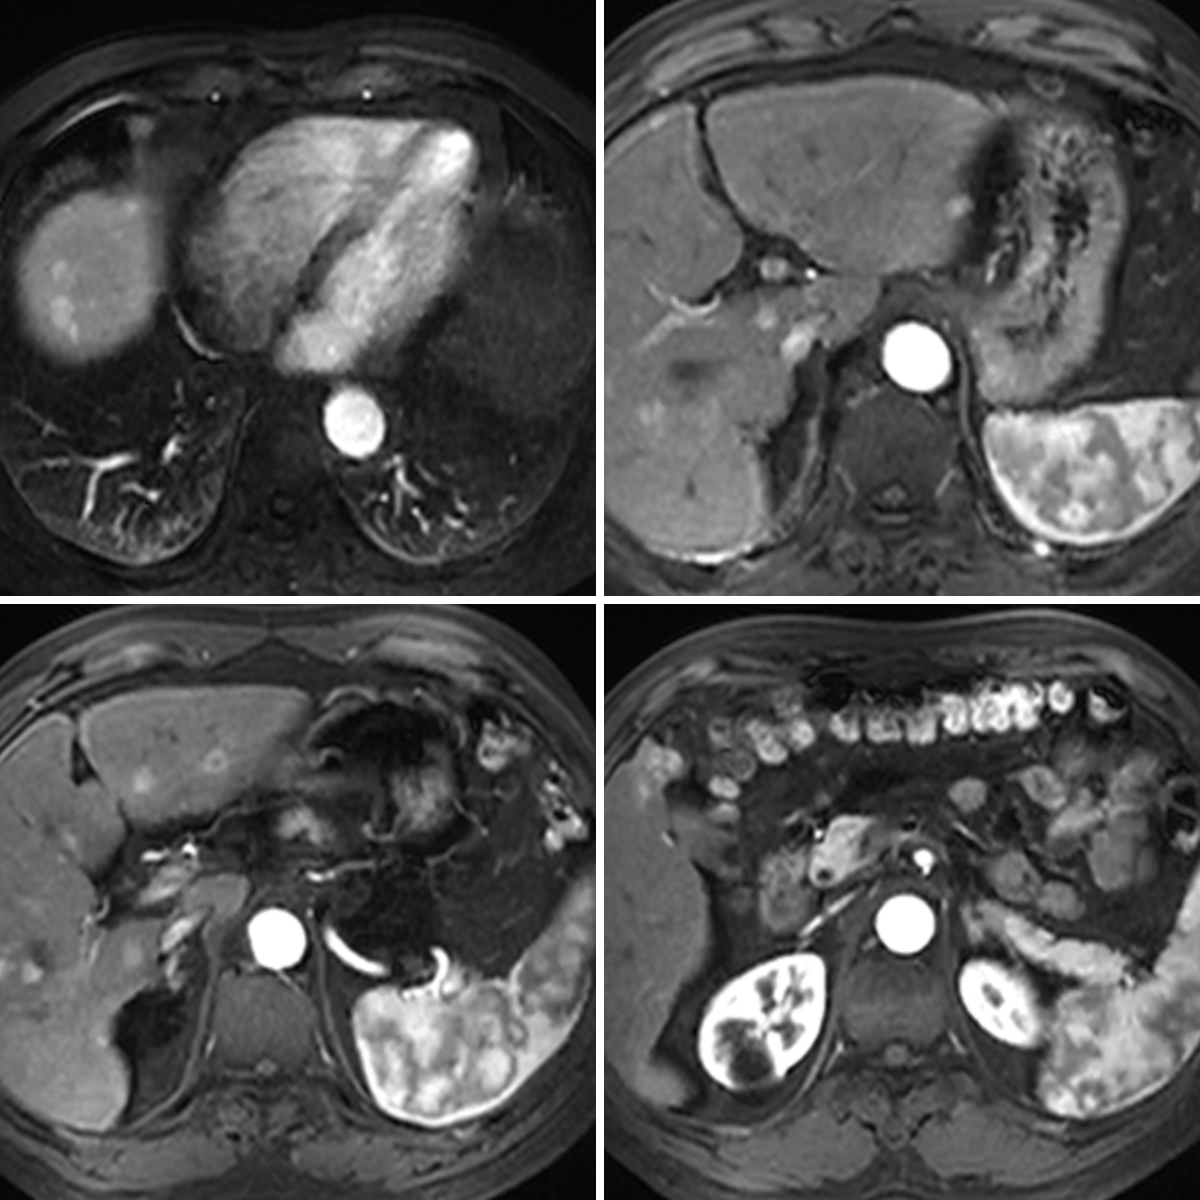

病历资料:患者男,55岁,2年前发现肝脏肿瘤,经过多家大型三甲医院的手术、介入、射频消融治疗,病情仍未得到有效控制,并逐渐恶化进展为肝脏弥漫性肿瘤病灶。2024年5月份患者前来我院就诊。增强MRI显示肝脏弥漫性“快进快出”病灶,符合多发肝癌表现。我院肝胆疾病团队针对该病例进行了多学科讨论,认为单一治疗手段很难控制肿瘤进展,应该调整患者治疗方案为介入+靶向+免疫多举措抗肿瘤治疗。

(治疗前)